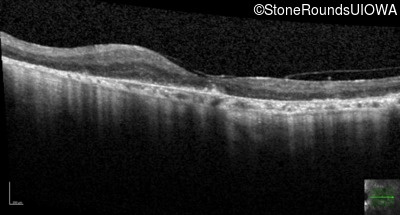

Age at visit: 64 years